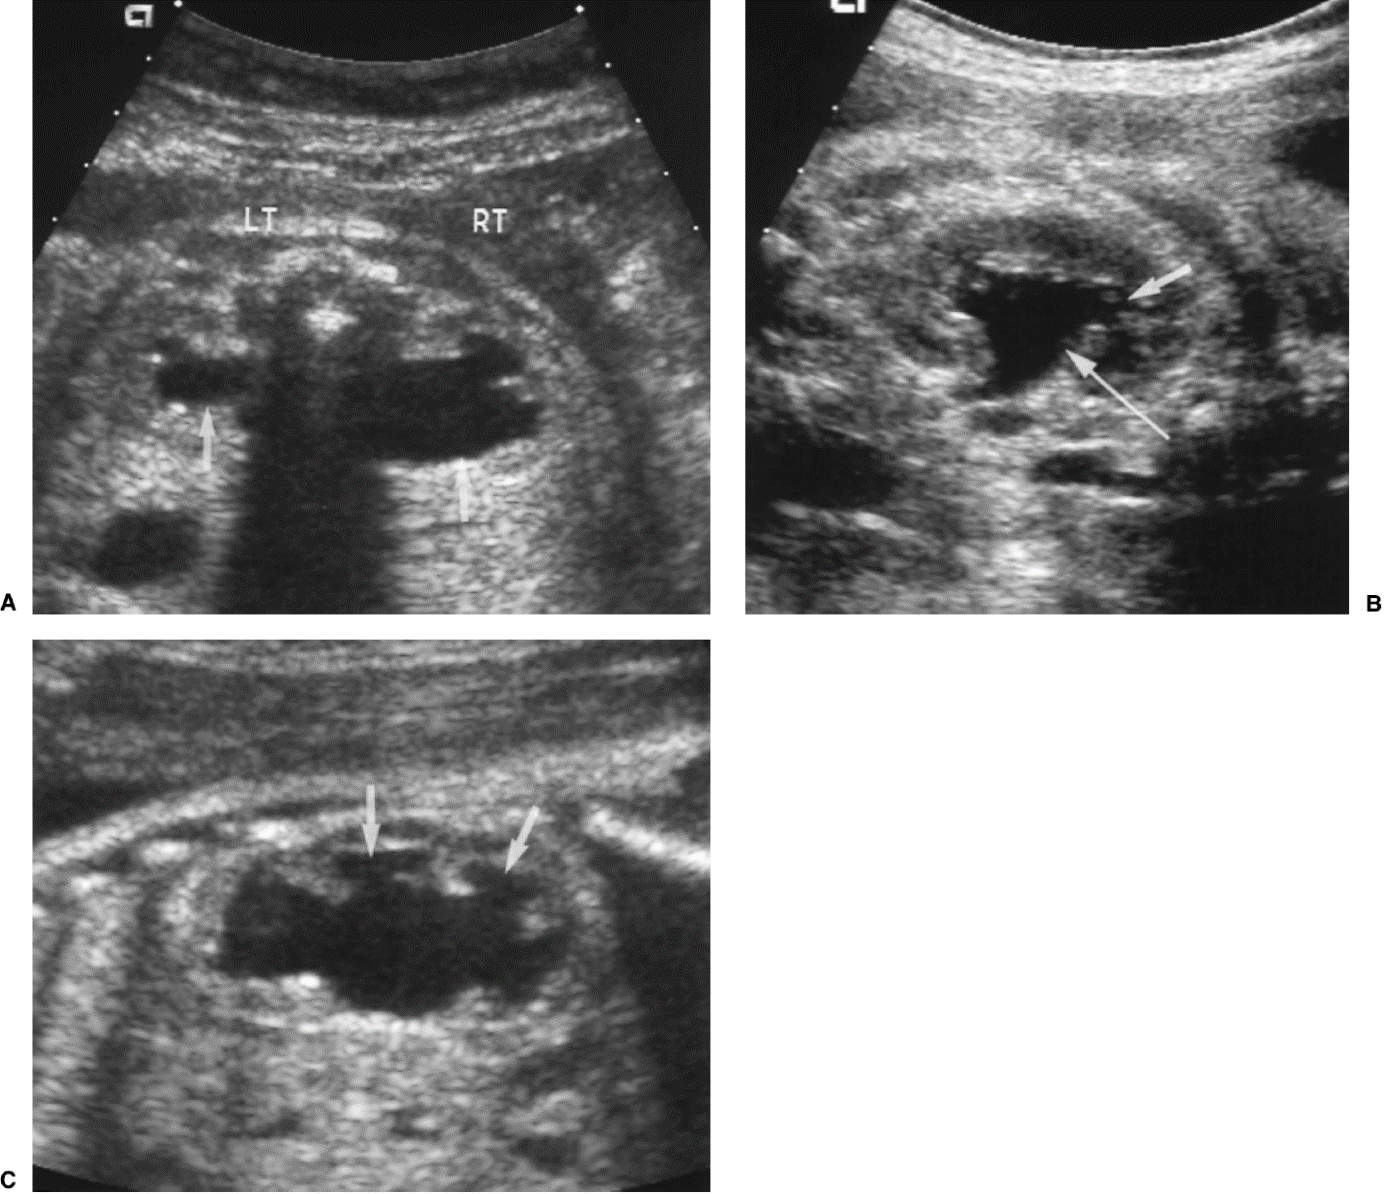

20 weken echografie: links: dikwandige blaas met verwijding van de plasbuis tot aan de kleppen (pijl): het “sleutelgat teken”. Onder: verwijde urineleiders. Bij kinderen gaan de urineleiders bij verwijding ook erg gekronkeld verlopen.

Verwijde nierbekkens (lange pijl) en nierkelkjes (korte pijl). Smalle nierschors.